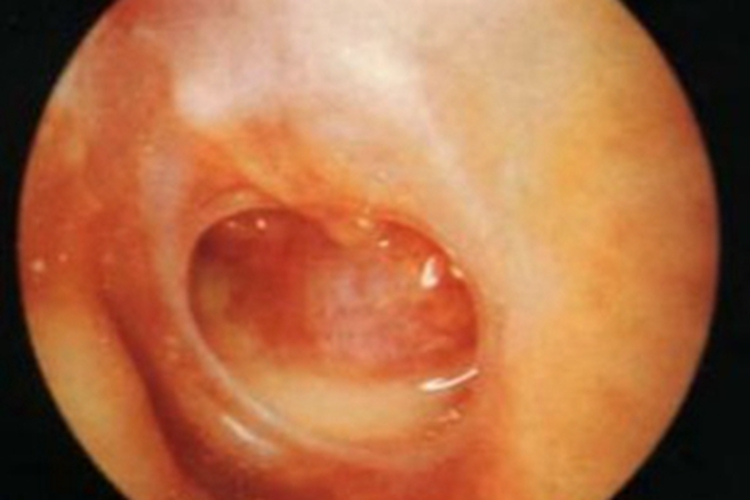

急性化脓性中耳炎患者鼓膜穿孔后,可出现外耳道渗液,可见黄白色的黏脓性分泌物渗出,可伴耳深部锐痛或波动性跳痛,还可出现畏寒、发热、怠倦、食欲减退等全身症状。